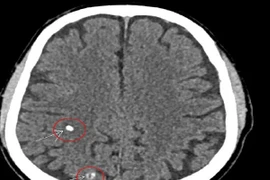

Mới đây, Trung tâm y tế huyện Thanh Sơn (Phú Thọ) đã tiếp nhận người bệnh Đ.V.C. (66 tuổi, trú tại xã Thượng Cửu, huyện Thanh Sơn) trong tình trạng cổ to bất thường, kèm theo chóng mặt, đau đầu.